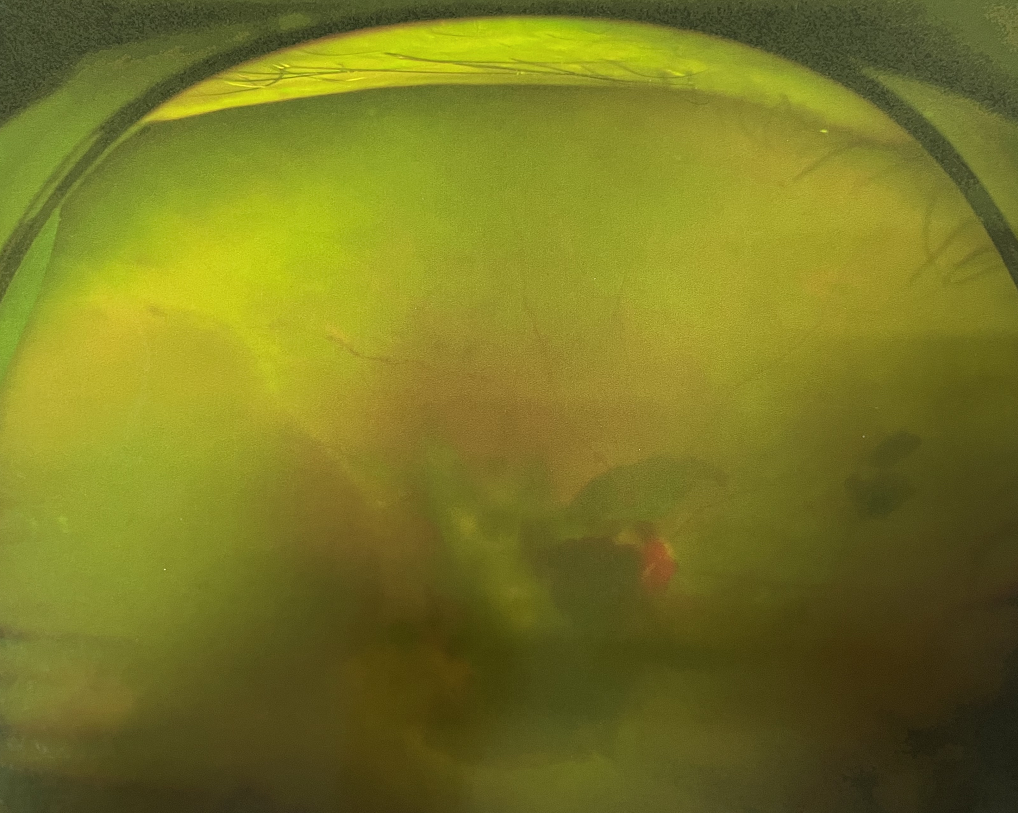

眼底出血不是獨(dú)立的眼病,而是由于眼球自己的病變和某些全身疾病的并發(fā)癥導(dǎo)致眼底的視網(wǎng)膜或脈絡(luò)膜出血,如果出血量大就會(huì)進(jìn)入到眼球的玻璃體內(nèi),從而影響視力,如果沒有得到恰當(dāng)?shù)闹委熆蓭砀鼑?yán)重的并發(fā)癥造成失明。

眼底出血的患者,如果出血量少,而且在視網(wǎng)膜周邊部可能沒有明顯癥狀,患者僅感到眼前有黑影浮動(dòng);如出血量多,將嚴(yán)重影響視力,甚至完全被黑影所遮擋僅剩光感;如出血位于視網(wǎng)膜的黃斑區(qū),患者視野中心區(qū)被暗影遮擋,周邊尚有部分視力。

先是散瞳檢查眼底,可以明確眼底出血的性質(zhì),出血部位和出血量有多少。眼B超檢查,對于眼底出血量特別多,無法看清眼底的患者,就需要進(jìn)行眼部B超檢查,以了解出血量,出血部位、有無合并視網(wǎng)膜脫離;還可以明確是否患有視網(wǎng)膜或脈絡(luò)膜的腫瘤。